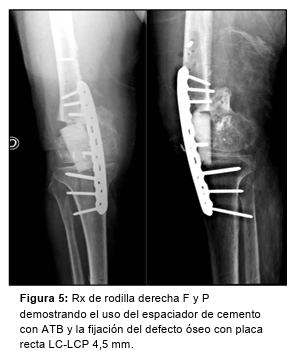

En un primer tiempo, tras un abordaje anterior recto sobre la rodilla se reseca la fibrosis, se abre cápsula y se toman nuevamente muestras para cultivos, encontrándose líquido, metalosis y severo daño condral y troclear femoral. Luego se realiza osteotomía al fémur distal, con liberación a medial y lateral, y elongación del miembro con distractor transarticular (Figura 4). Se coloca un espaciador de cemento con ATB y fijación con placa recta LC-LCP 4,5 mm (Figura 5).